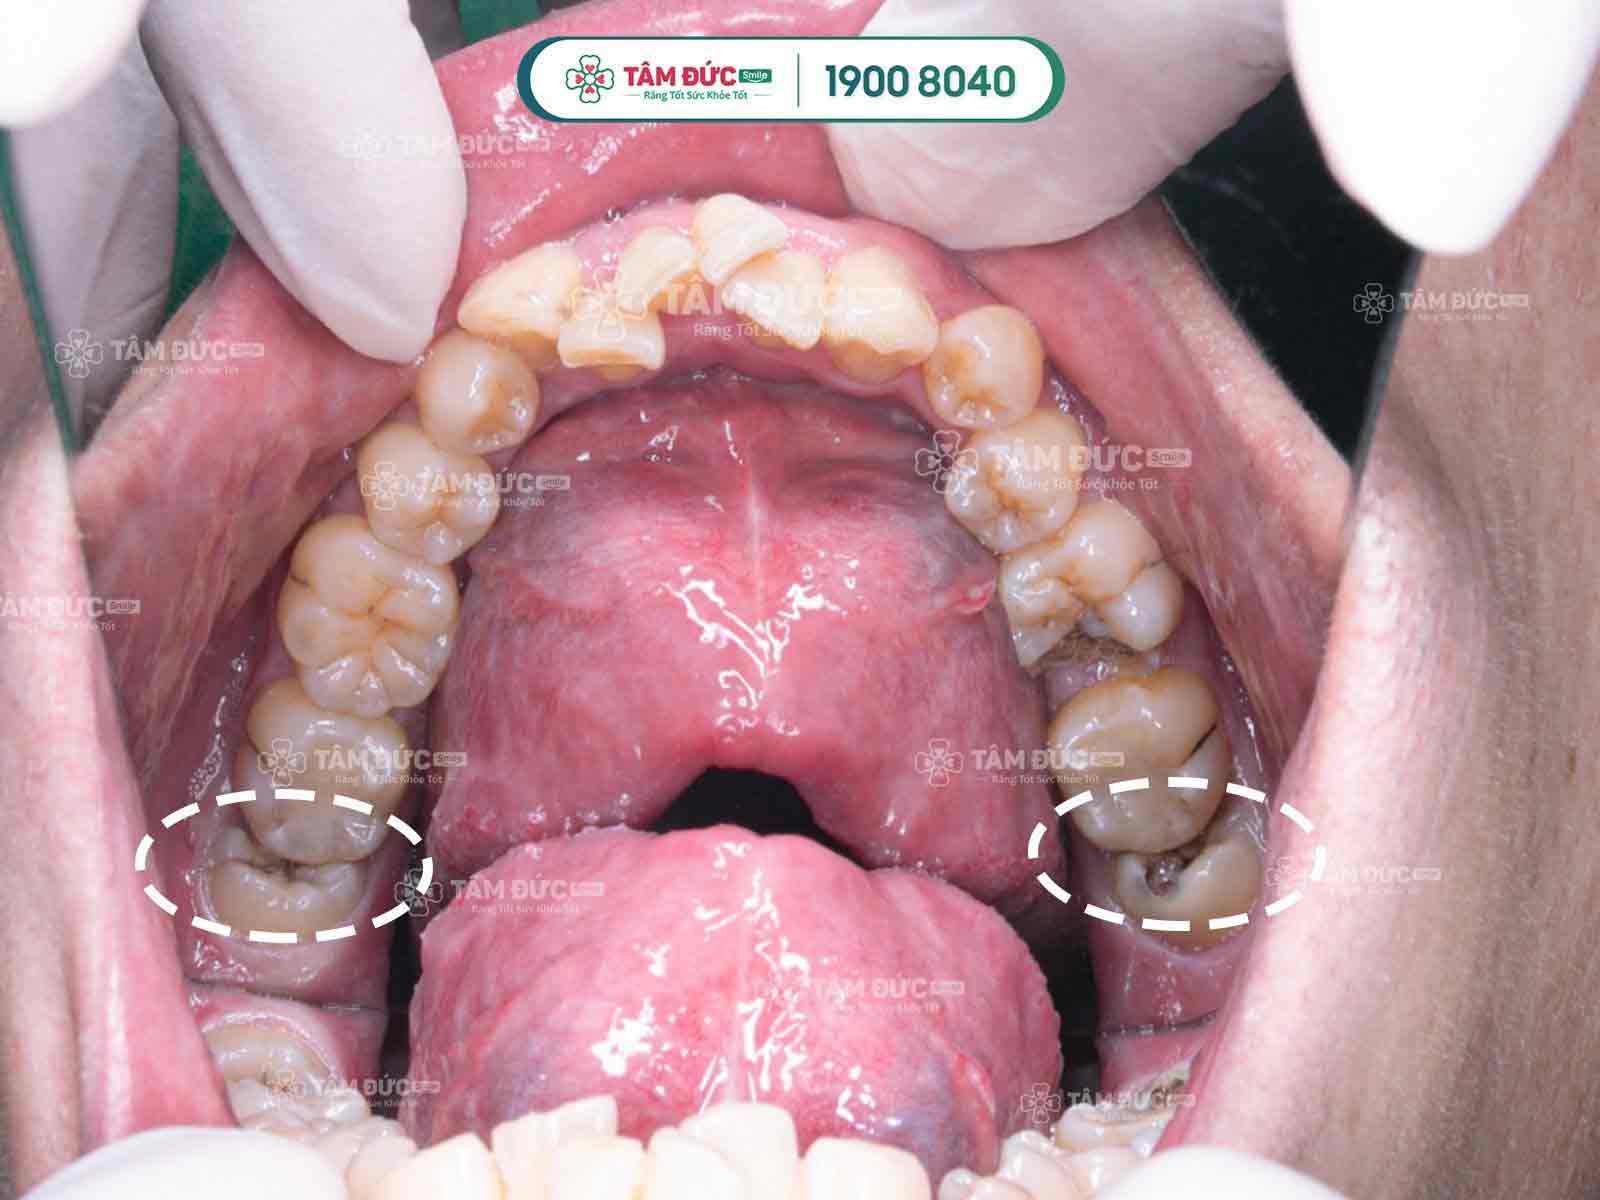

1.1 Các dạng răng khôn mọc lệch thường gặp

- Răng khôn mọc lệch má.

- Răng khôn mọc ngược vào phía xương hàm.

- Răng khôn mọc lệch và kẹt vào răng số 7.

- Răng khôn mọc ngầm trong xương hàm.

1.2.3. Sâu răng khôn

Vị trí răng khôn bị lệch là nơi rất khó vệ sinh, tạo điều kiện cho nhiều loại vi khuẩn có hại sinh sôi và phát triển, gây sâu răng, viêm nướu, viêm nha chu, tích tụ ổ mủ.